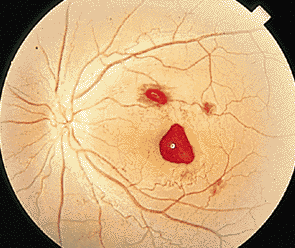

對于很多患者而言,玻璃體變性主要原因就是隨著年齡不斷增加,新陳代謝不斷變緩,使得玻璃體自身變性。比如像星狀玻璃體變性,常常見于50歲以上,不過它只是引起視力的不適,并不會導致視力下降。因為玻璃體內新陳代謝緩慢,而出現(xiàn)了含鈣的脂質白色小球。而玻璃體變性中更為嚴重的是出現(xiàn)液化現(xiàn)象,特別是閃輝性玻璃體液化,由于嚴重眼外傷和手術后眼內出血導致的玻璃體或前房會出現(xiàn)無數(shù)黃白色和其他顏色的膽固醇結晶。

對于玻璃體混濁這樣復雜的癥狀,一般的眼科醫(yī)院無法根治,由于眼睛玻璃體的特殊性,目前尚無有玻璃體變性的特效藥,只能經過長期的治療和鞏固,使得玻璃體不會出現(xiàn)其他病變。所以對于病情較為嚴重的玻璃體變性患者而言,就像因為變性引發(fā)的視網膜剝離或玻璃體出血等等,這些會出現(xiàn)視力嚴重減退,眼睛發(fā)紅、疼痛、畏光等等,一定要到專業(yè)的眼科醫(yī)院進行醫(yī)治,比如在廈門眼科醫(yī)院的眼底??疲D陙沓搜鄣撞≈?,玻璃體變性治療領域在全國也是處于領先位置。